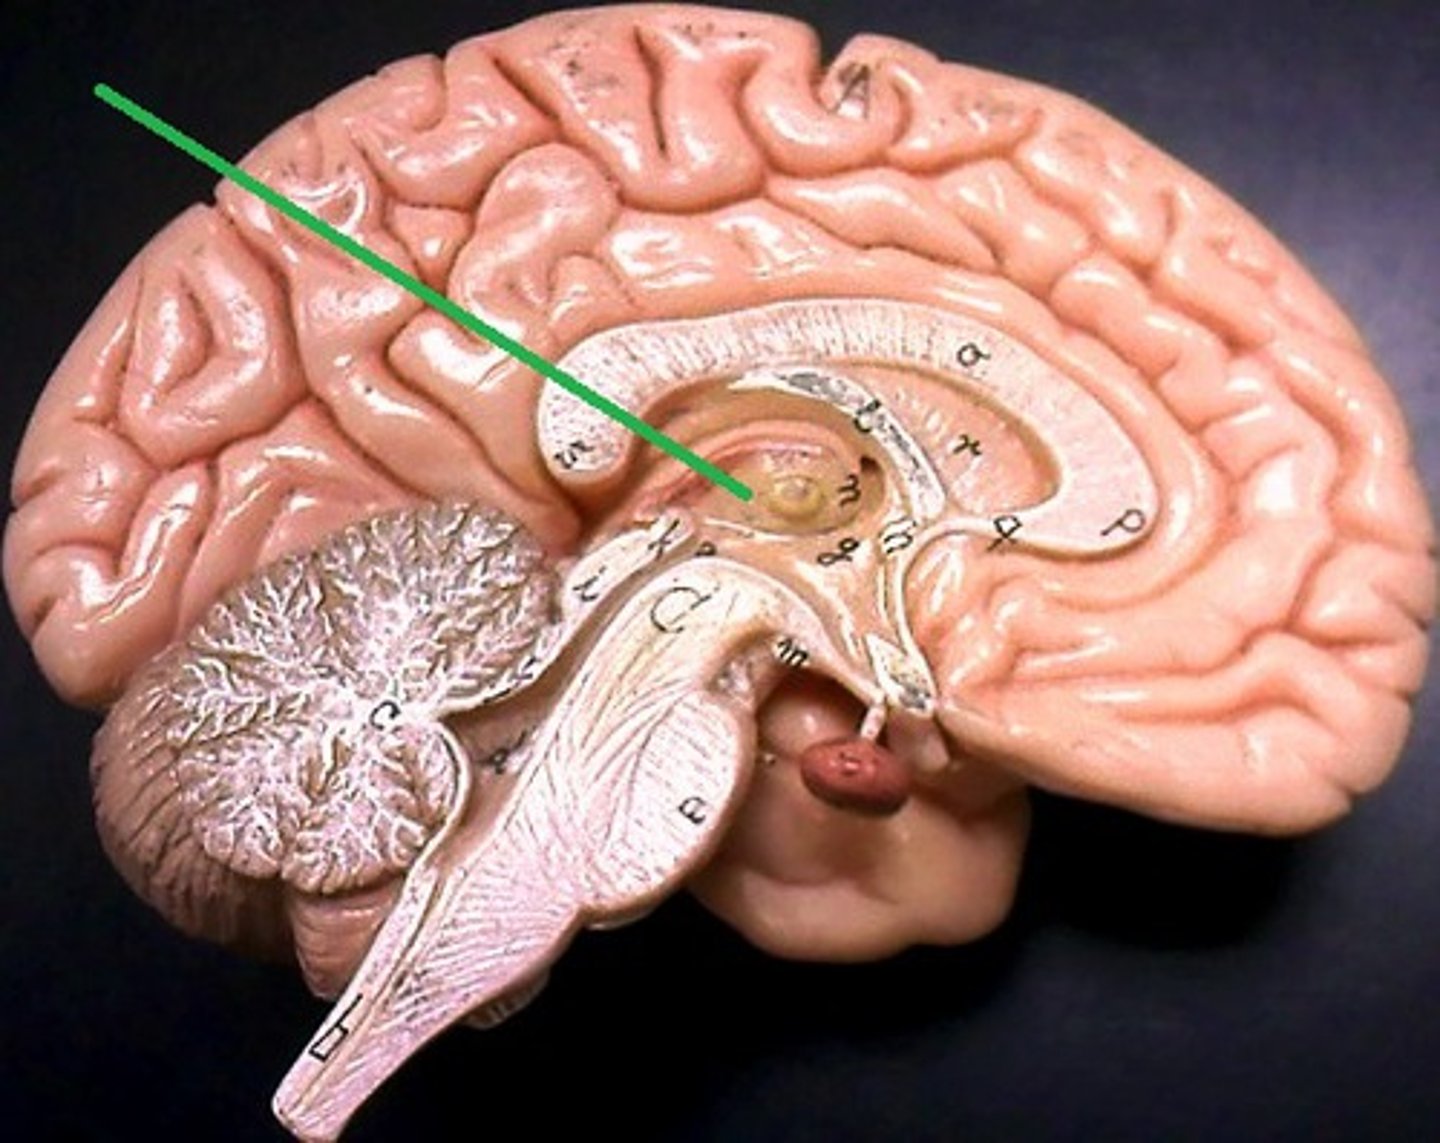

Diencephalon

Sits on top of the brain stem,

Enclosed by the cerebral hemispheres,

Made up of 3 parts: the Thalamus, Hypothalamus, and Epithalamus

Thalamus

Bilateral egg-shaped nuclei, which forms superolateral walls 3rd ventricle,

Relay station for information coming into cerebral cortex:

-Will sort and edit the info

-Also provides a crude recognition of sensation as pleasant or unpleasant before it sends info on to cortex where specific stimulus localization and discrimination still occur

Hypothalamus

Located under thalamus where it caps the brain stem and forms inferolateral walls of 3rd ventricle,

Main visceral (involuntary) control center of body is vitally important to overall body homeostasis (few tissues in body escape its influence),

hypothalamus chief homeostasis controls

1) Important autonomic (ANS) control center,

2) Center for emotional response (limbic system),

3)Regulates Body tempt., food intake, water balance and thirst, and sleep-wake cycle

4) Control of endocrine system functioning: pituitary gland

Pituitary gland

Is attached to the hypothalamus and the hypothalamus is therefore indirectly influences many body functions by sending signals through to regulate its secretion of hormones

Epithalamus

Forms the roof of the 3rd ventricle,

Houses the pineal gland or body (an endocrine gland) (Melatonin production: sleep/wake cycle),

Includes the choroid plexus (forms cerebrospinal fluid- CSF)